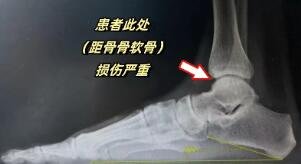

软骨损伤

由于韧带损伤导致经常崴脚,小尹的左踝软骨严重磨损,几乎被“磨平”,出现了“骨对骨”硬摩擦的情况,这不仅严重影响他的行动,而且带来很大的痛苦。